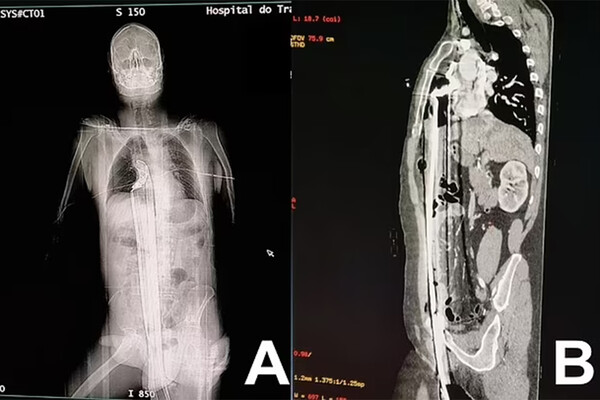

Инцидент произошел на стройплощадке в городе Куритиба: 57-летний рабочий находился на строительных лесах, когда поскользнулся и полетел вниз. Падение пришлось на торчавший металлический штырь, который пронзил мужчину вдоль: штырь вошел через пах, поразил печень и достиг верхней части диафрагмы, едва не задев сердце.

Мужчину на скорой доставили в больницу, где врачи по частям достали из него штырь, зашили раны и сделали переливание крови. Через два дня пациента перевели из реанимации в общую палату: к этому моменту он самостоятельно передвигался и принимал пищу.

Пациента выписали на 12-й день, позже ему провели операцию, чтобы восстановить поврежденную часть уретры, на которой образовался рубец.